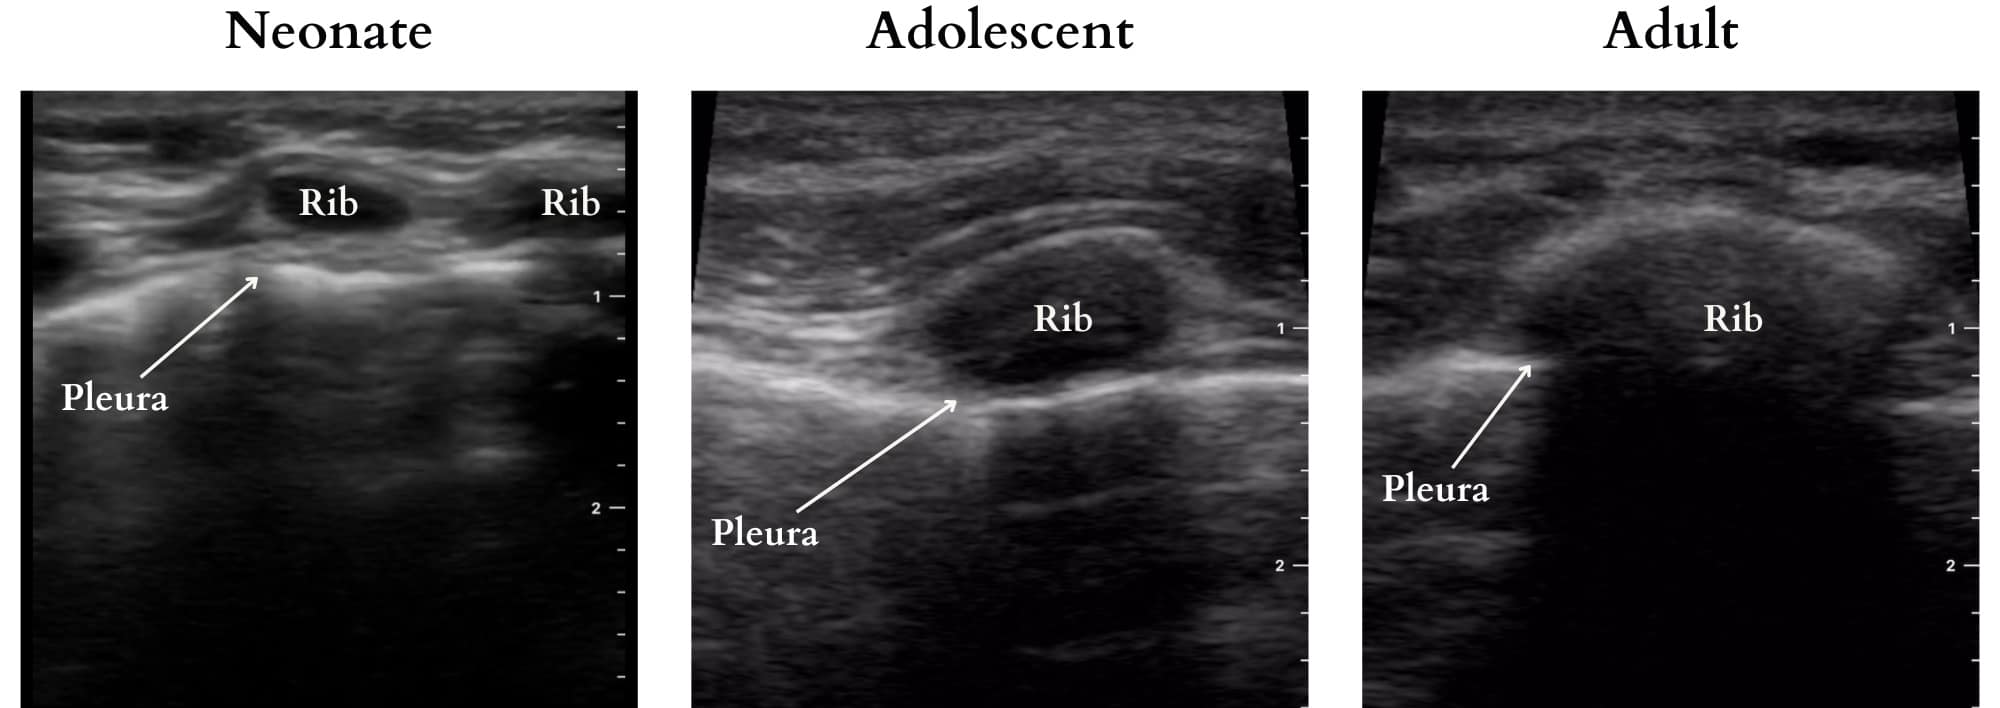

The normal lung is an air-filled structure comprised of alveoli, a rich microvascular network, and interstitium. The difference in acoustic impedance between these components generates sonographic artefacts that can be interpreted. In adults and older children, acoustic widows must be found, typically between ribs, through the abdomen, or at the supraclavicular fossa. However, transcostal imaging is feasible in neonates and infants due to their less mineralized, cartilaginous ribs (Figure 2). Comprehensive LUS requires imaging of the entire chest to ensure a complete assessment as a single sonographic image only represents that specific location.

Figure 2. Transcostal imaging highlighting ultrasound penetrability in pediatric patients across age groups.

Reproduced with permission from baby-blocks.com